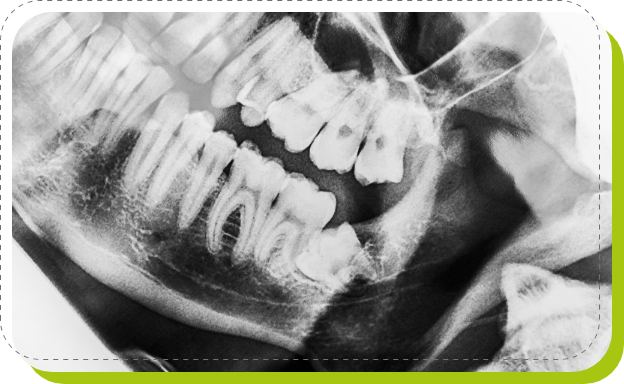

親しらずがまっすぐほかの歯と同じ方向で生えてきていて、まわりの歯に悪影響を与えていない場合は、そのままほかの歯と同じように扱います。「歯ぐきの中に埋まったままの親しらず」や「途中まで生えて止まっている親しらず」は、レントゲン撮影なので、これからの生え方などをある程度予測できることがあります。痛みや腫れなどに気づかない場合でも、ほかの歯の根を押していることもありますが、これは見た目ではわかりません。検査を行い診察しなければ、抜歯が必要か、そのまま残すのかを診断はできないのです。